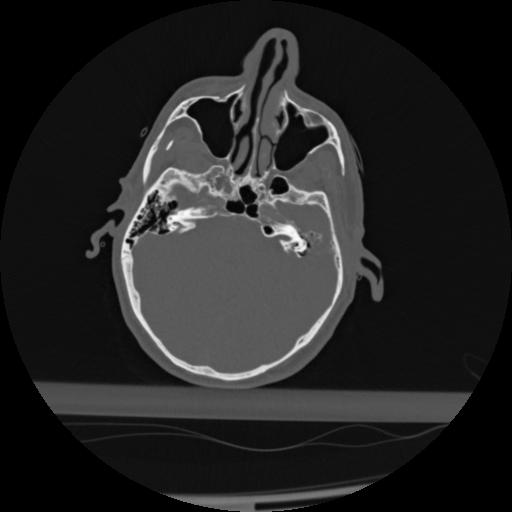

22 ANGIO,CE,Vol,0.5,ANGIO,,